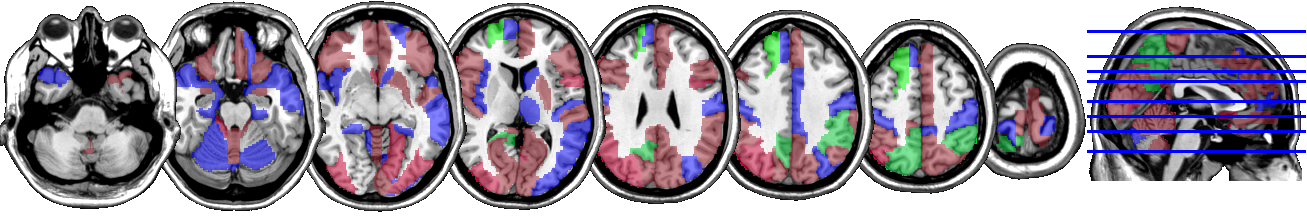

One motivating example for our methods is the application to the functional magnetic resonance imaging (fMRI). The dataset consists of the functional signals of the brain activities measured by blood-oxygen-level-dependent (BOLD), which detects hemodynamic changes based on the metabolic demands followed by neural activities. There are pre-specified regions of the brain, and the BOLD signals associated with multiple voxels in each region are integrated into one signal for that region. Thus, the fMRI data are considered to be multivariate functional data in which each functional predictor represents the signals from a region of the brain. In Section 8, we regress the ADHD index to the regional BOLD activities of the fMRI of the human subjects. There are regions of the brain in the data, and our methods reduce the regions to 41 regions with significantly lower errors than the linear functional regression. Figure 1 displays the regions of the brain’s atlas that are identified by our method. It shows that the methods simplify the data analysis and provide clear representation while keeping the crucial information. The analysis shows that there is an urgent need for new methods in the fields of medical and life sciences as well as other related areas.

In Figure 4 and Figure 5, we display the regions associated with the estimated active sets for IQ and ADHD by the MFG-LASSO respectively. The final active sets of the algorithms were extracted, and matched with the AAL’s atlas where each of the regions has a label. The regions were manually entered into the WFU picked atlas Maldjian and et al. (2003) tool of the SPM-12 ran on MATLAB 2020b to produce mask.nii files. The mask files were imported on MRIcron software to produce the multi-slice images.

The active sets cover the regions associated with IQ in Yoon and et al. (2017) such as cerebello-parietal component and the frontal component. It is mentioned in the paper that the parietal and the frontal regions are strongly associated with intelligence by maintaining a connection with the cerebellum and the temporal regions. The shaded areas cover the ones mentioned in Goriounova and Mansvelder (2019) as well. We provide the name of the regions associated with these active sets in the appendix.

It is interesting that ADHD and IQ have a large proportion of common active sets. For instance, when MFG-LASSO is applied, they overlap in ROIs where the size of active sets are and for IQ and ADHD respectively. On the other hand, the ROIs that are associated with ADHD but not with IQ are the middle and superior frontal, the Parahippocampal, the inferior parietal, and the superior temporal pole gyri. The ratio of the number of right hemisphere regions to the left ones associated with IQ is significantly greater than that of ADHD.